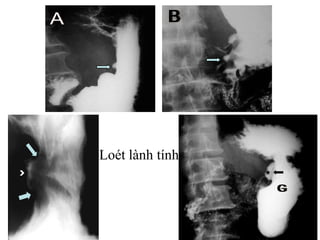

LOÉT DẠ DÀY

Loét lành tính

Loét hành tá tràng lành tính

Loét hành tátràng lành tính